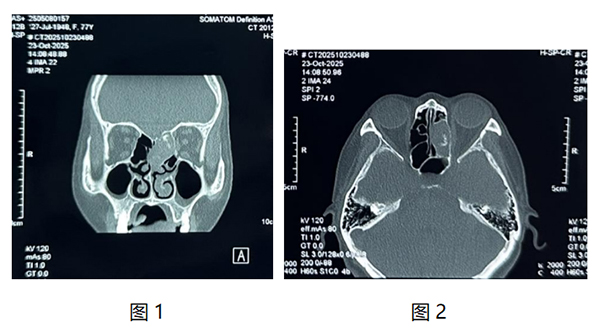

我(wo)院耳鼻咽喉頭頸外科(ke)近日(ri)爲(wei)一(yi)名(míng)77歲老年(nian)患者實施鼻內(nei)鏡下篩窦開放+窦內(nei)病變清(qing)除術(shù),患者因“左側頭痛多(duo)涕1月”到(dao)我(wo)院檢(jian)查,入院查體(ti)可(kě)見左側鼻腔中(zhong)鼻甲水腫,上鼻道大(da)量棕黃色幹痂。鼻窦CT檢(jian)查可(kě)見左側篩窦內(nei)軟組織影,內(nei)部(bu)密度不均。(如圖1、2)